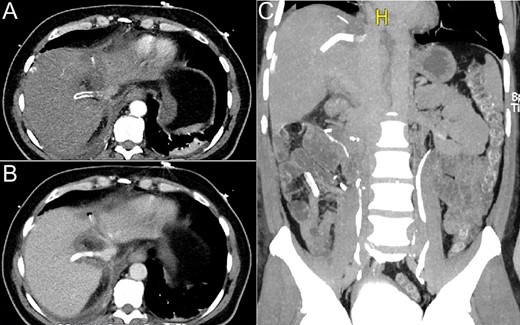

Double antiaggregant therapy was initiated on the second post-operative day with clopidogrel (75 mg orally daily) and aspirin (100 mg orally daily). One month after the procedure, clopidogrel was interrupted and aspirin maintained as single-antiplatelet therapy. Doppler US on post-operative Day 2 showed normal blood flow in the graft. Contrast-enhanced CT scans performed on post-operative Day 5 and 3 months after the procedure showed a properly positioned and patent graft (Fig. 6).

CT scan performed on the fifth post-operative day: (A) axial view, no intravenous contrast; (B) axial view, intravenous contrast inside the graft and (C) coronal view, graft filled with contrast.